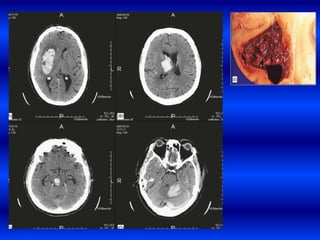

Pte masculino, raza negra,

APP de HTA que sufre una

HIP subcortical derecha

que en los primeros

80mtos presenta cefalea,

disartria ligera y

hemiparesía izquierda en

la segunda TAC hay un

deterioro progresivo de la

conciencia , midriasis

derecha por hernia uncal y

apertura a ventrículos

laterales.

EXPANSIÓN TEMPRANA DE HIC. Ptemasculino, raza negra, APP de HTA que sufre una HIP subcortical derecha que en los primeros 80mtos presenta cefalea, disartria ligera y hemiparesía izquierda en la segunda TAC hay un deterioro progresivo de la conciencia , midriasis derecha por hernia uncal y apertura a ventrículos laterales.